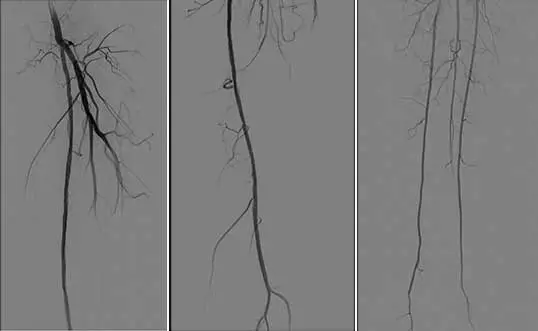

5、使用Matrix Super PTX (巴泰醫療)5mm*20cm及5mm*15cm約束型藥物涂層球囊全程擴張左股淺動脈病變。

6、復查造影見:左股淺動脈血流通暢,殘余狹窄小于 30%,左下肢血供明顯改善,撤出鞘管,封合器封合右股動脈穿刺點,安返病房。